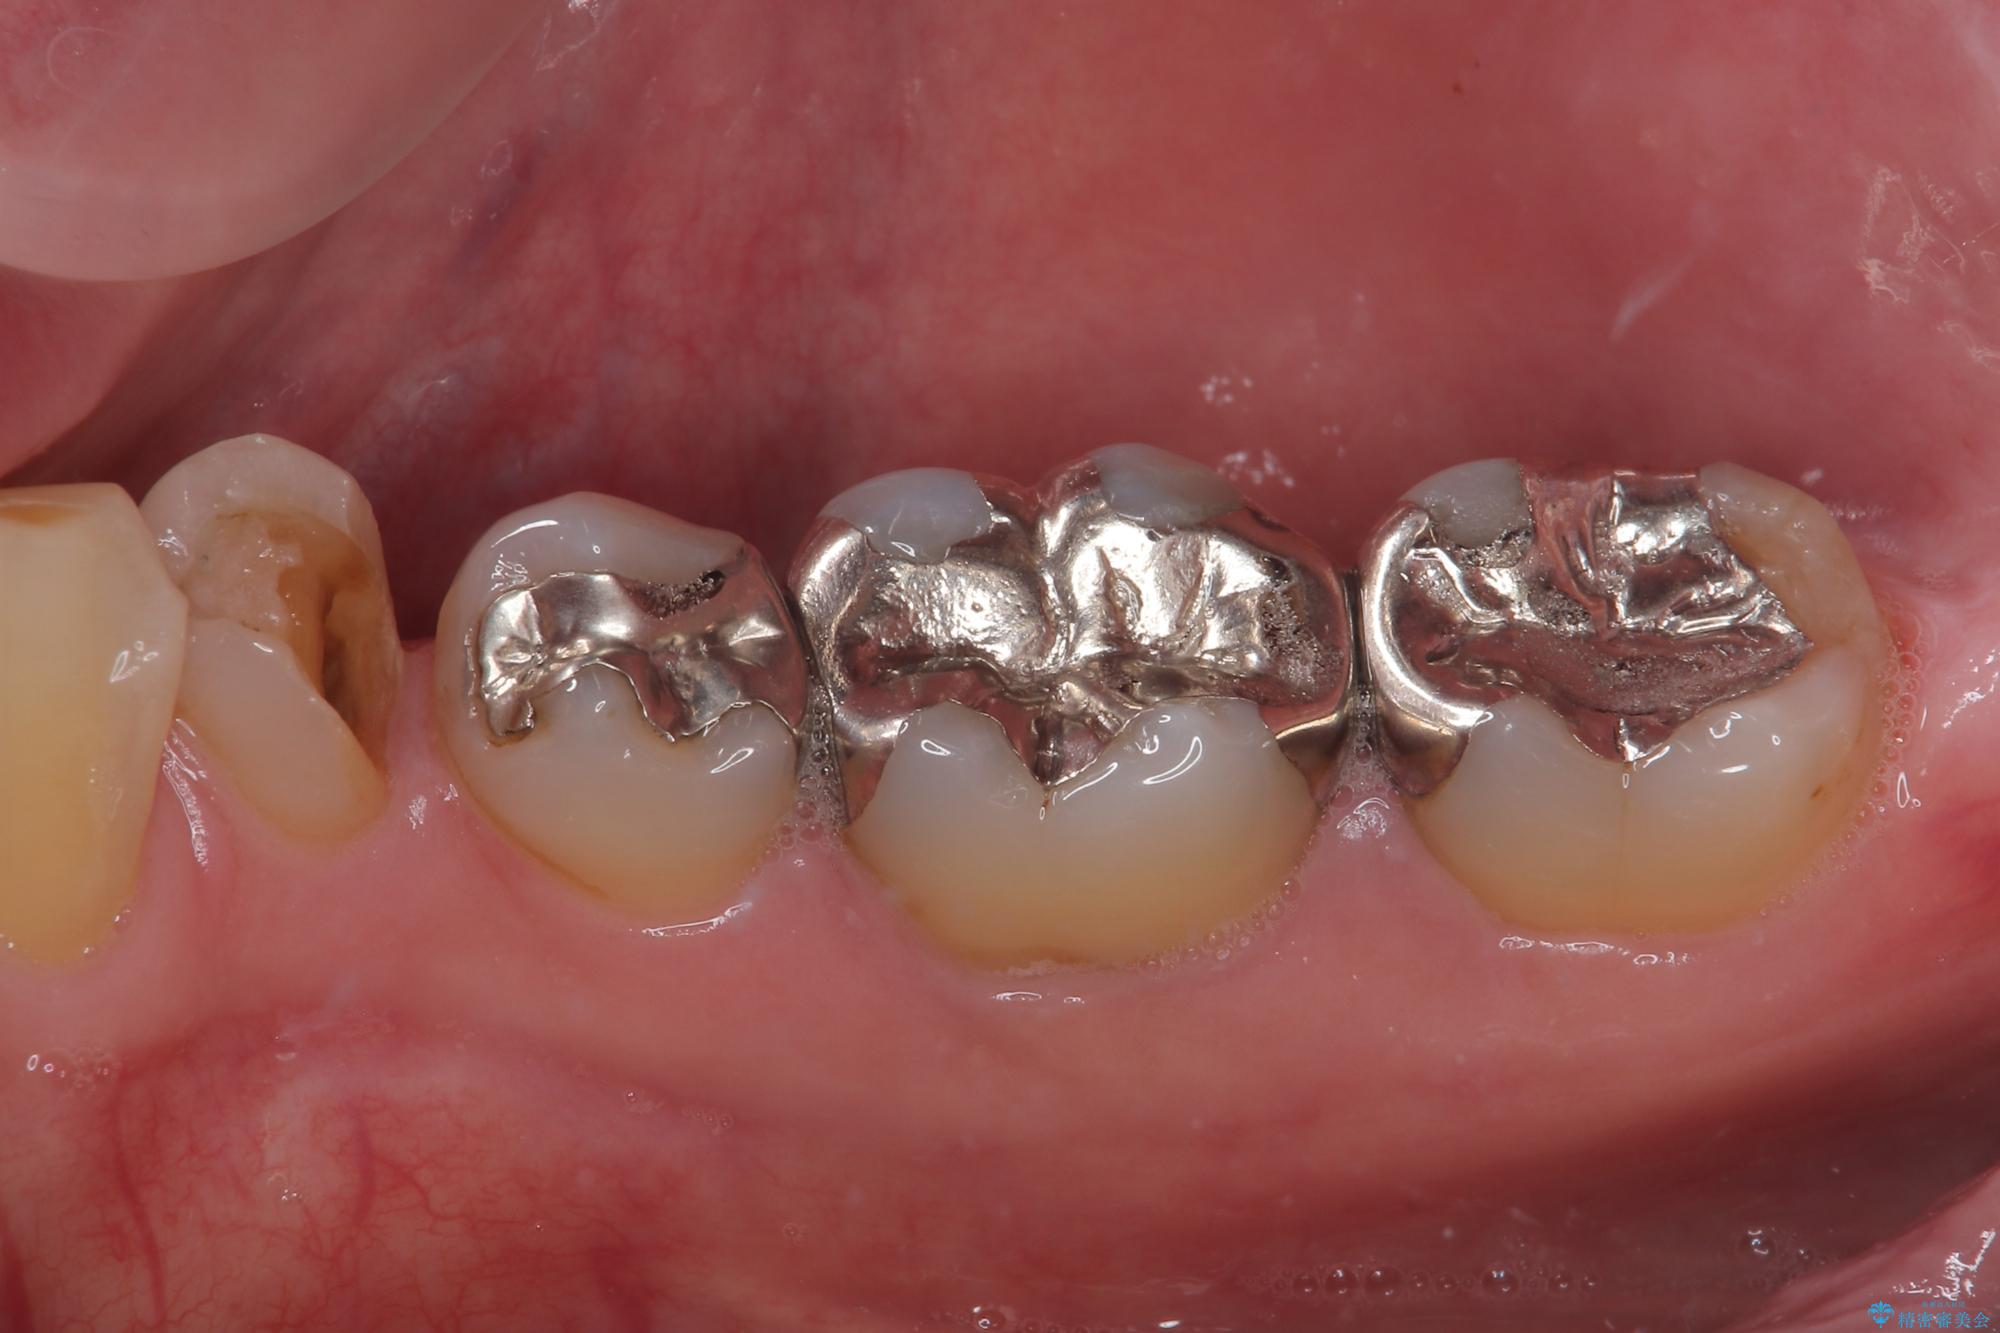

審美面、機能面共に満足していただけました。

順次、後ろにある不適合のメタルインレーの部位をやり替えていく予定です。